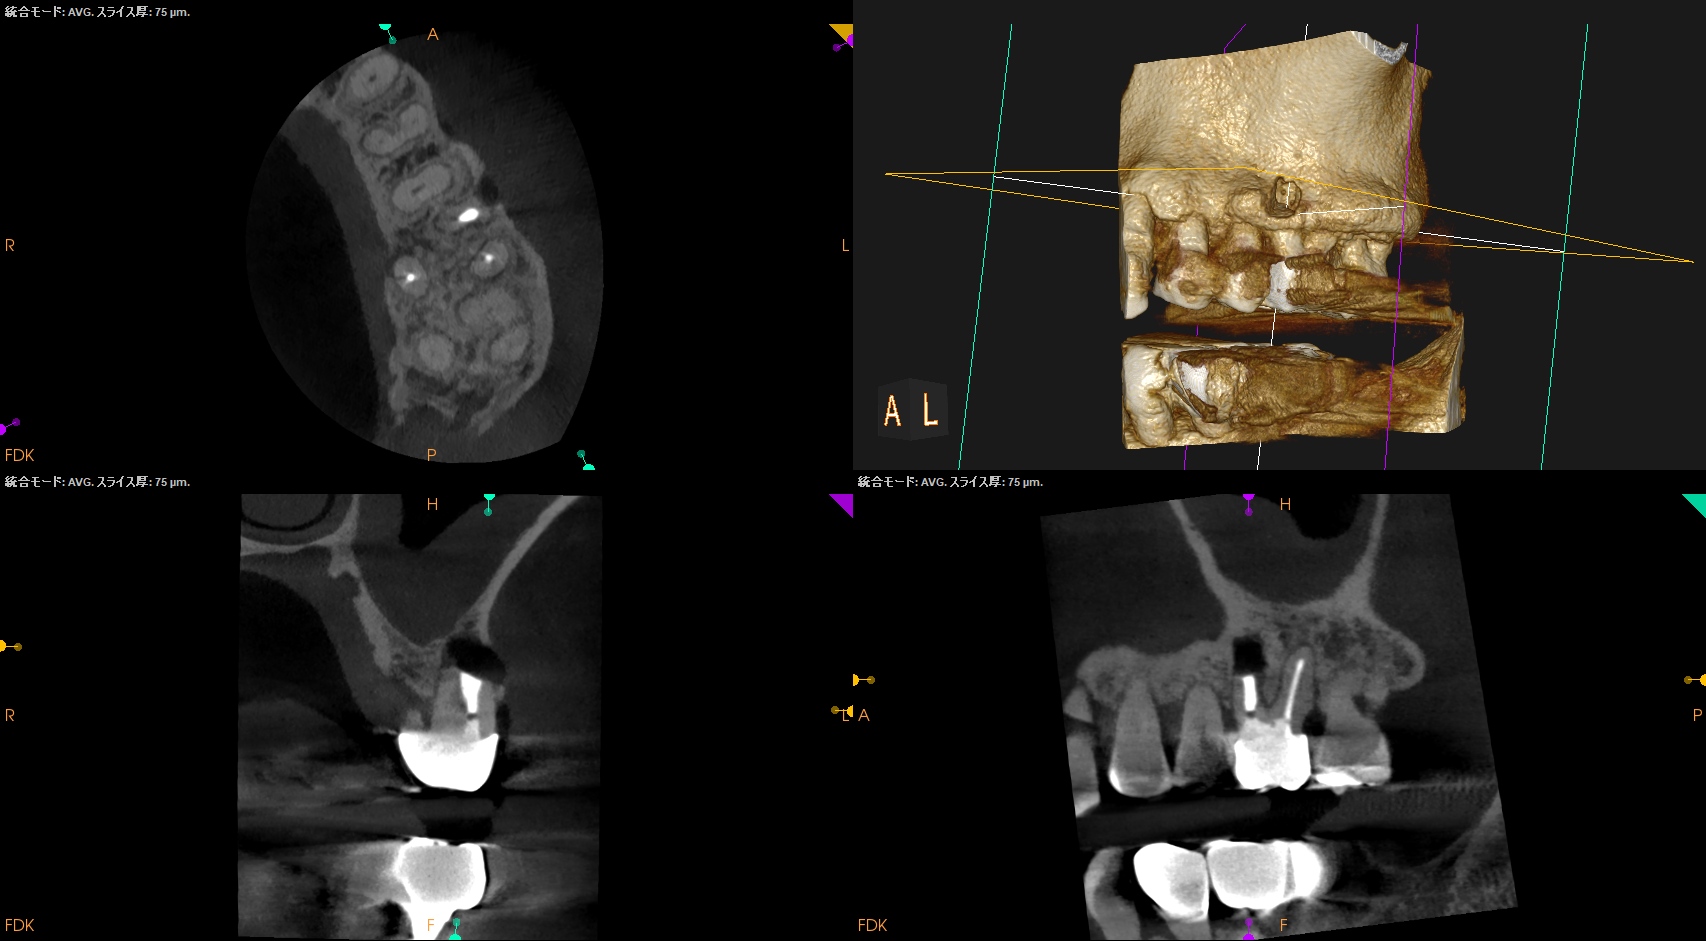

歯軸と並行になるようにCBCTのバーを動かした。

すると…

このような絵になる。

ここを、

こうすべきだろうか?

それともこのままで

いいだろうか?

中心に対して左右非対称に近くなることから私は修正しない道を選択した。

この状態でOKと判断したのである。

さて、この日の記事で言いたいことは私の処置に対する正当性の主張ではなく、

CBCTを正しく動かして診断できるような絵にできるのか?

ということに尽きる。